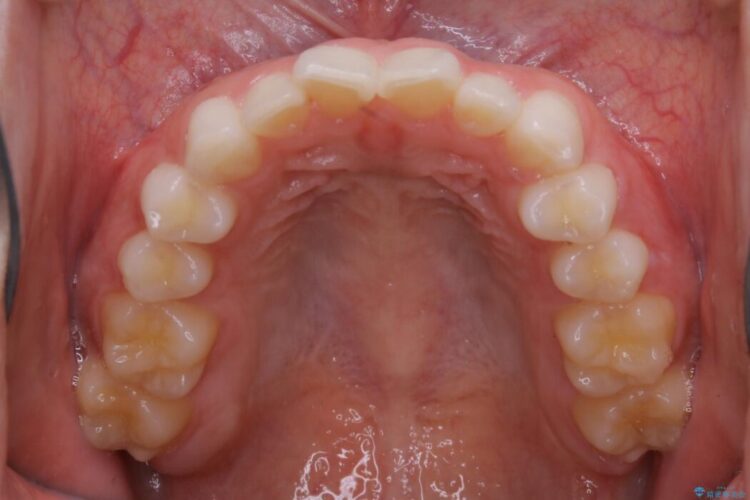

上下前歯のねじれなどで生じている歯列のガタつきをなおしたいとのことで来院されました。

精密検査をしたところ、奥歯に大きな問題がないため移動はほとんど必要がなく、また主訴であるガタつきの改善に必要なスペースも少量であったため、インビザラインのライトパッケージの治療をご提案しました。

半年という短期間でスピード治療が完了しました。